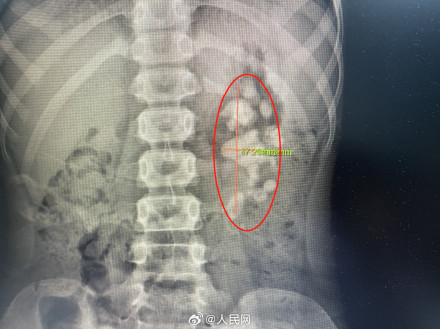

近日,广州,一10岁男孩腰痛,并伴有尿频、尿痛,呕吐等症状。医生发现大大小小形态各异的结石“合体”成一块“鹿角型”结石,塞满了孩子的左肾。据悉,该结石属于铸型结石,属于最难治疗的肾结石类型之一,手术难度高、风险非常大。最终,医生成功取净结石,最大程度保障了患儿的肾功能及生命安全。(广州医科大学附属第一医院)